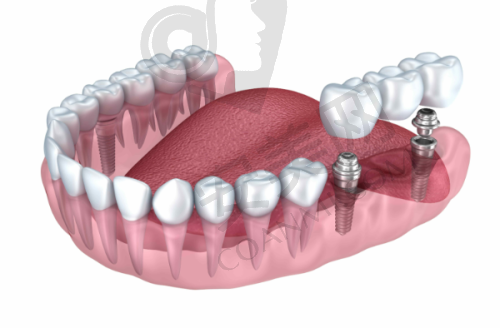

韩国登腾种植牙是韩国登腾公司研发生产的一款种植牙产品。它采用了精良的种植技术和优质的材料,旨在为患者提供更接近自然牙齿功能和美观的解决方案。登腾种植牙的种植体表面经过特殊处理,能够更好地与人体牙槽骨相结合,大大提高了种植的成功几率。而且它的设计符合人体口腔的生理结构,佩戴起来更加舒适,能够有效修复牙齿的咀嚼功能。在海内外范围内,韩国登腾种植牙都受到了特别多患者和医生的认可。在长春中诺口腔,医生会根据每位患者的具体口腔情况,精细地为患者选择合适的登腾种植牙型号,确保种植成效达到至佳。

安装牙冠:种植体植入牙槽骨后,需要等待一段时间让种植体与牙槽骨充分结合。这个过程一般需要3 - 6个月左右,具体时间会根据患者的个人情况有所不同。当种植体与牙槽骨结合牢固后,医生会为患者安装牙冠,至此,种植牙手术全部完成。